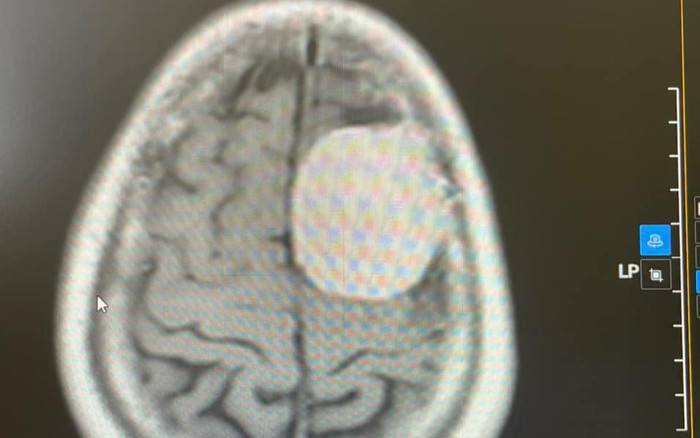

Các bác sĩ phát hiện một khối u có kích thước 36x48x54mm vùng trán đỉnh trái của người bệnh. (Ảnh: BV Đa khoa Bắc Giang).

Sau khi vào khoa Ngoại thần kinh của Bệnh viện Đa khoa tỉnh, bác sĩ đã tiến hành khám và chỉ định chụp cộng hưởng từ có tiêm thuốc cản quang để tìm nguyên nhân, kết quả phát hiện một khối u có kích thước 36x48x54mm vùng trán đỉnh trái của người bệnh.